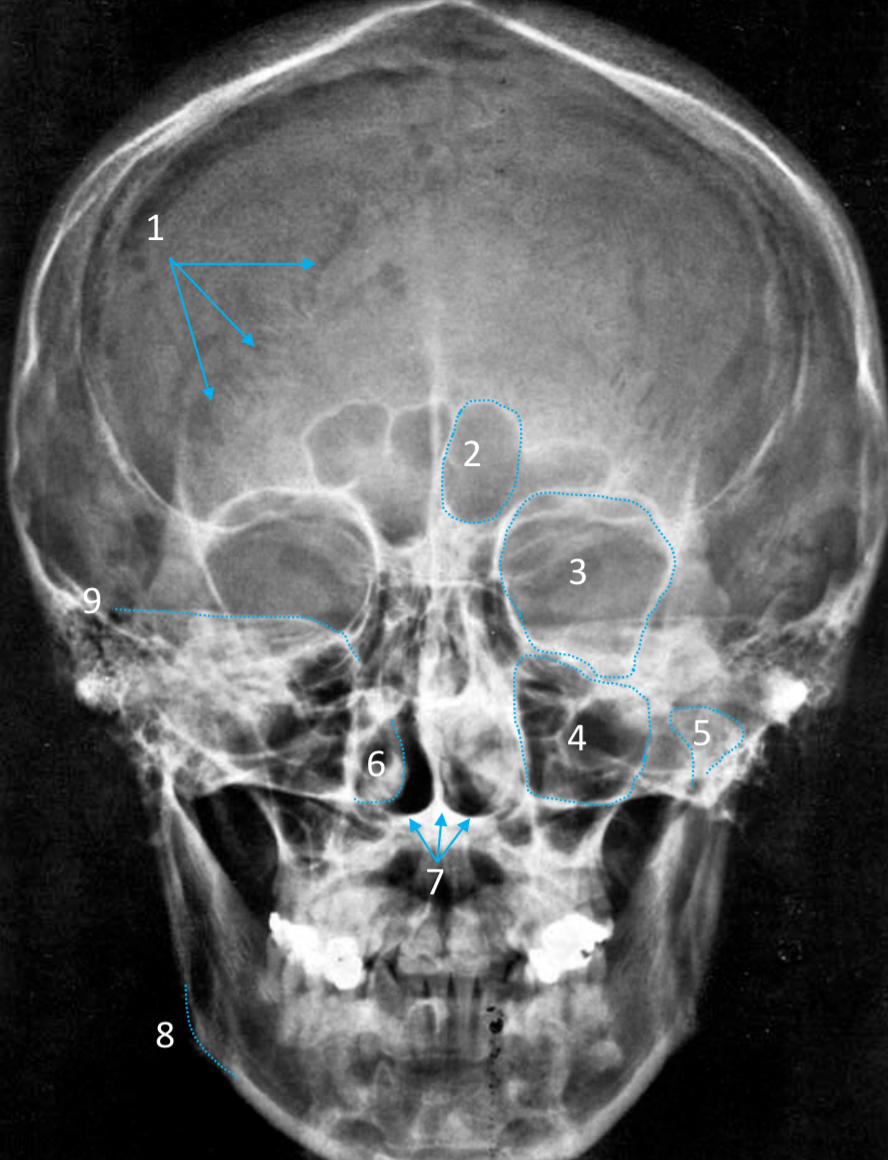

Mandible

ID bone

Maxilla

ID bone

Frontal sinus

ID structure

Pituitary fossa

ID structure

Occipital

ID bone

Lambdoid suture

ID structure

Frontal sinus

ID structure

Orbital margin

Orbit

Maxillary sinus

ID structure

Mandibular condyle

ID structure

Inferior nasal concha

ID structure

Hard palate

ID strucutre

Gonial angle

ID strucutre

Petrous ridge

ID structure

Groove of middle meningeal a.

ID structure

Roof of orbit

ID structure

Frontal sinus

ID structure

Pituitary fossa

ID structure

Petrous ridge

ID structure

Sphenoid sinus

ID structure

Hard palate

ID structure

Mastoid air cells

ID structure

Zygomatic arch

ID structure

Mandibular condyle

ID structure

External auditory meatus

ID structure

Mastoid air cells

ID structure

Foramen magnum

ID structure

Foramen ovale

ID structure

Foramen spinosum

ID structure